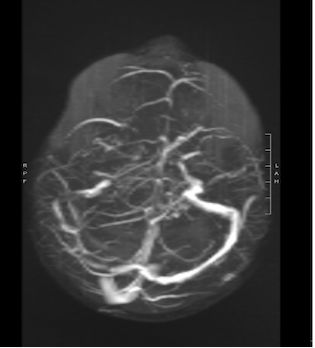

In considerazione della storia clinica, i bambini venivano sottoposti a RM che evidenziava in entrambi i casi un quadro di trombosi venosa cerebrale, con estensione nel primo caso al seno trasverso, sigmoideo e bulbo della giugulare destro, in associazione alla presenza di segni di flogosi a carico delle cellette mastoidee (Figura 1), mentre nel secondo caso trombosi subacuta con coinvolgimento di seno trasverso, sigmoideo, bulbo, tratto craniale della giugulare interna e sospetto iniziale impegno della vena di Labbé a sinistra, senza flogosi mastoidea (Figura 2).